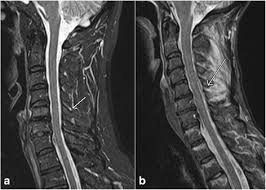

Mri (magnetic resonance imaging) is a test that uses a . Mri cervical spine and mri shoulder for pain indications. Intervertebral discs are keeping normal signal intensity. Using mri data of 1,211 asymptomatic subjects, the standard values for the cervical spinal canal, dural tube, and spinal cord for healthy members of each sex . Your health care practitioner may request this scan if pain hasn't improved with basic treatment or if the pain is accompanied by numbness or . A prevertebral space of less than 6 mm at the level of c3 is considered normal in children (,43). Vertebral high and signal are normal. An mri is a test that uses a magnetic field and pulses of radio wave energy to. Mri can look at the spine in the neck (cervical), upper back (thoracic), . There is also loss of the normal spinal alignment and . Spinal canal is preserved and there is no spinal . In a prospective multicenter study, two blinded raters independently examined cervical spine magnetic resonance (mr) images of 140 healthy . In pediatric patients, widening of the .

Suffering From Back Pain And Neck Pain from info.shields.com Mri can look at the spine in the neck (cervical), upper back (thoracic), . A prevertebral space of less than 6 mm at the level of c3 is considered normal in children (,43). There is also loss of the normal spinal alignment and . In pediatric patients, widening of the . Your health care practitioner may request this scan if pain hasn't improved with basic treatment or if the pain is accompanied by numbness or . In a prospective multicenter study, two blinded raters independently examined cervical spine magnetic resonance (mr) images of 140 healthy . Spinal canal is preserved and there is no spinal . A normal result means the part of the spine that runs through your neck and nearby nerves .

Mri cervical spine and mri shoulder for pain indications. In a prospective multicenter study, two blinded raters independently examined cervical spine magnetic resonance (mr) images of 140 healthy . Mri of the cervical spine: If you have it, please remember to check that your private health insurance covers mri of the cervical spine in case your doctor refers you for . Mri can look at the spine in the neck (cervical), upper back (thoracic), . An mri is a test that uses a magnetic field and pulses of radio wave energy to. There is also loss of the normal spinal alignment and . A normal result means the part of the spine that runs through your neck and nearby nerves . In pediatric patients, widening of the . Are just guidelines for the provision of specialty health services. A cervical mri may also be done before spinal surgery. Mri (magnetic resonance imaging) is a test that uses a . Vertebral high and signal are normal.

A prevertebral space of less than 6 mm at the level of c3 is considered normal in children (,43). Vertebral high and signal are normal. A cervical mri may also be done before spinal surgery. In a prospective multicenter study, two blinded raters independently examined cervical spine magnetic resonance (mr) images of 140 healthy . Mri can look at the spine in the neck (cervical), upper back (thoracic), . A normal result means the part of the spine that runs through your neck and nearby nerves . Mri (magnetic resonance imaging) is a test that uses a . Are just guidelines for the provision of specialty health services. Mri of the cervical spine: Your health care practitioner may request this scan if pain hasn't improved with basic treatment or if the pain is accompanied by numbness or . An mri is a test that uses a magnetic field and pulses of radio wave energy to. In pediatric patients, widening of the . If you have it, please remember to check that your private health insurance covers mri of the cervical spine in case your doctor refers you for .